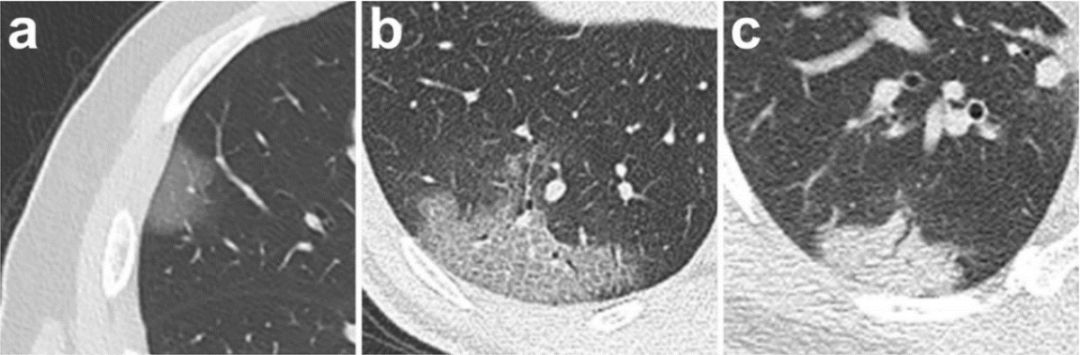

在武漢協(xié)和醫(yī)生們的建議下,飛利浦科學(xué)家與兄弟團隊針對新冠肺炎的CT影像學(xué)特點及臨床需求,整合IntelliSpace Portal后處理工作站中COPD(慢阻肺分析)、LNA(肺結(jié)節(jié)分析)、Liver(肝臟分析)、MMTT(多平臺多時間追蹤分析)等多個模塊的功能,在面對數(shù)萬病人數(shù)據(jù)時,為醫(yī)生們?nèi)嬖u估與追蹤病人影像表現(xiàn)提供了一個可行的預(yù)案,讓醫(yī)生們從繁重的閱片工作中解脫出來、將更多的精力投入到對疾病本身的研究以及對病人的關(guān)懷。(下圖是由武漢協(xié)和醫(yī)院提供的典型病例)

【1】 Pan Feng, Ye Tianhe, …, Zheng Chuansheng. Time course of lung changes on chest CT during recovery from 2019 Novel Coronavirus (COVID-19) pneumonia. DOI: 10.1148/radiol.2020200370